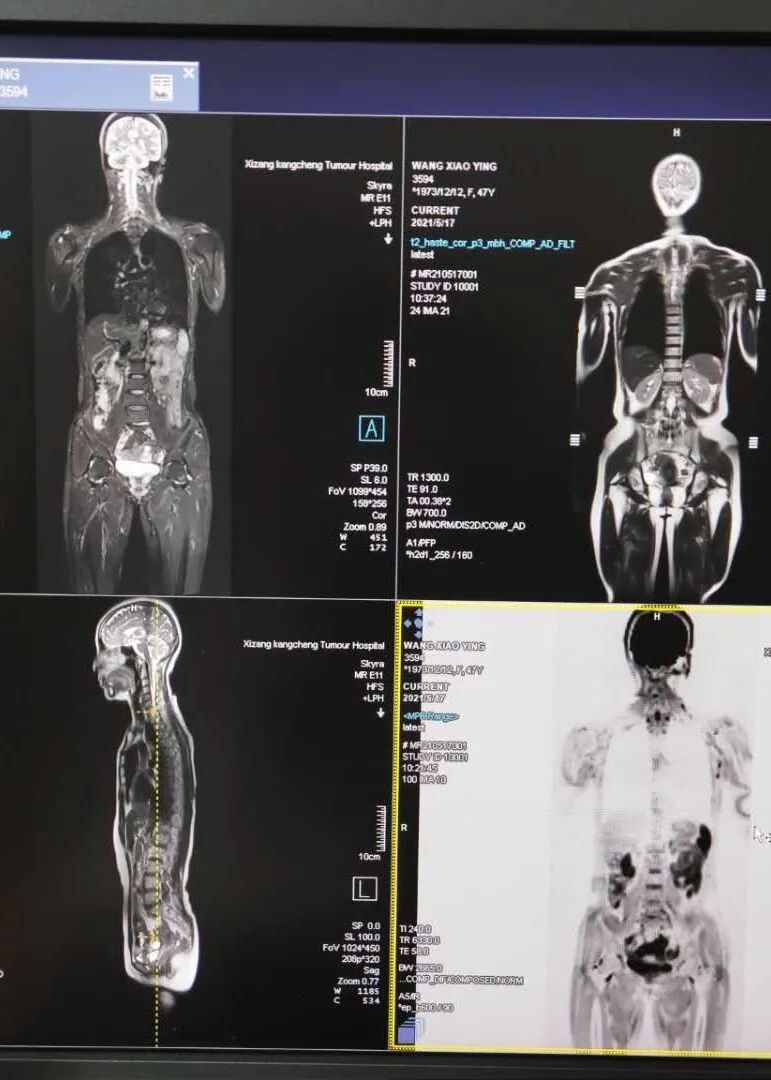

图片

全身弥散加权成像

DWIBS在淋巴瘤分期中的应用

DWIBS在评估淋巴瘤骨髓浸润中的应用

DWIBS在淋巴瘤疗效评估中的应用